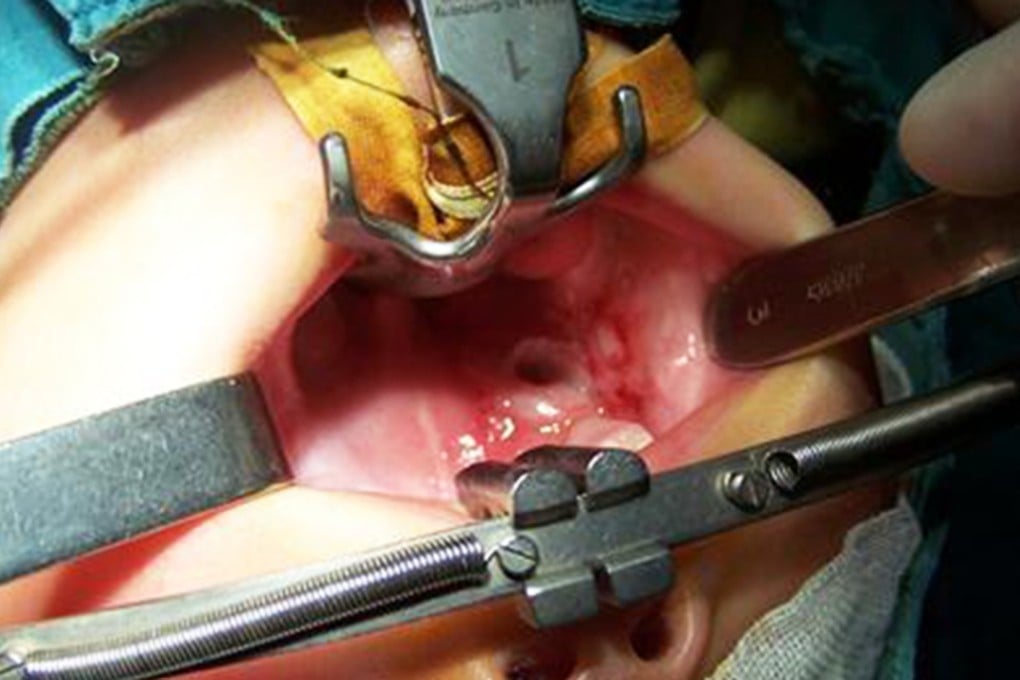

Fortunately, no traces of the battery were found in Xuan Xuan’s stomach and surgeons sewed up her wound in a two-hour operation.